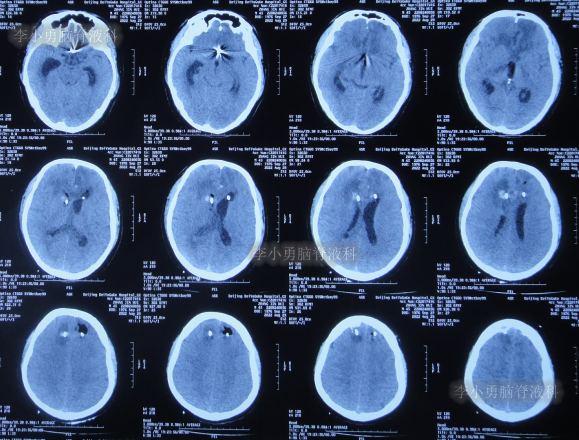

患者于2022年7月8日凌晨突发头痛,伴有胡言乱语,右下肢明显乏力,被家属送至附近的陕西省榆林市某医院,查头颅CT示脑出血(图-1),考虑脑动脉瘤破裂;当即给予了DSA检查发现前交通动脉瘤(图-2)。

图-1:2022年7月8日头颅CT